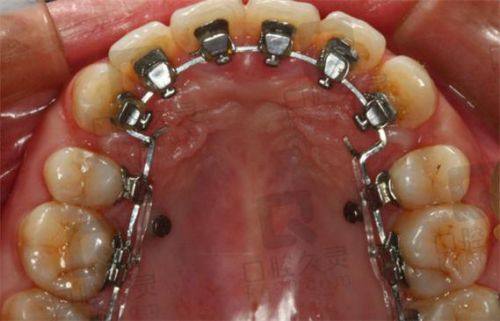

5. 种植牙:种植牙是一种较为精良的牙齿缺失修复方法。张亚科医生深谙各种种植体特性,能够根据患者的口腔条件和需求,选择合适的种植体。在种植过程中,他会严格遵循手术规范,确保种植的成功几率。术后,他会为患者提供详细的护理指导,帮助患者尽快修复。

3. 患者张先生,牙齿缺失多年,一直想进行种植牙修复。他了解到张亚科医生在种植牙方面技术不错,便前来就诊。张亚科医生为他进行了详细的口腔检查,根据他的口腔条件选择了合适的种植体。在种植手术过程中,张亚科医生操作精细,手术非常顺利。术后,张先生按照张亚科医生的指导进行护理,种植的牙齿特别快就修复了正常功能。张先生对张亚科医生的技术赞不绝口,他说:“张医生的种植牙技术真的特别厉害,手术过程一点都不疼,修复也特别快。现在我又能正常吃东西了,真的太感谢张医生了。”